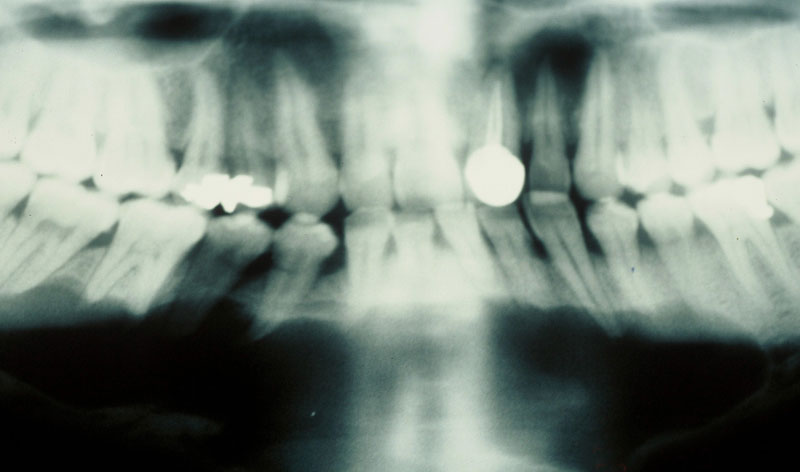

Su cirugía es sencilla y está basada en la extracción del quiste con criterios conservadores, y en la reconstrucción del defecto creado por la limpieza quirúrgica.